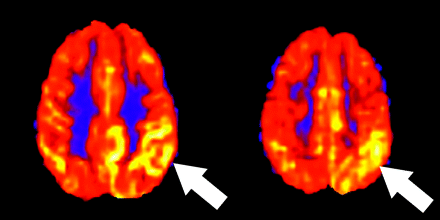

Seizure activity can mimic acute stroke in both imaging findings and clinical presentation. In the absence of restricted diffusion or a discrete lesion on conventional MR imaging, focally increased signal intensity on ASL may represent either a complex partial seizure in the postictal state (Fig 4) or clot lysis and late reperfusion in the setting of subacute stroke. Often the clinical history will allow differentiation of these 2 entities. Ictal single-photon emission CT has been shown to be 90% sensitive in the depiction of hyperperfusion in the ictal phase of temporal lobe epilepsy. In addition, in a meta-analysis by Lee et al,9 late postictal hyperperfusion was found in the epileptogenic zone in more than half of patients with seizures. ASL has advantages in that both anatomic and perfusion MR images can be obtained in the same setting. The mechanism of hyperperfusion due to seizure activity is not completely understood but may be related to transient loss of autoregulatory function in the surrounding vasculature or to the release of excitatory neurostimulators such as glutamate in areas of increased neuronal firing.9 In the seizure evaluation, ASL complements the traditional evaluation with electroencephalography (EEG), anatomic imaging, and nuclear medicine studies.

Hyperperfused seizure territory. A 6-year-old boy with a history of Landau-Kleffner syndrome who presented with complex partial seizures causing paresis of the right face and upper extremity. ASL shows regional hyperperfusion in the left parietal hemisphere associated with the ictal phase of seizure activity (arrows). EEG confirmed almost continuous seizure activity within the left hemisphere. Findings of the diffusion-weighted sequence were normal (not shown). Symptoms improved on antiepileptic medications and a course of intravenous immunoglobulin.